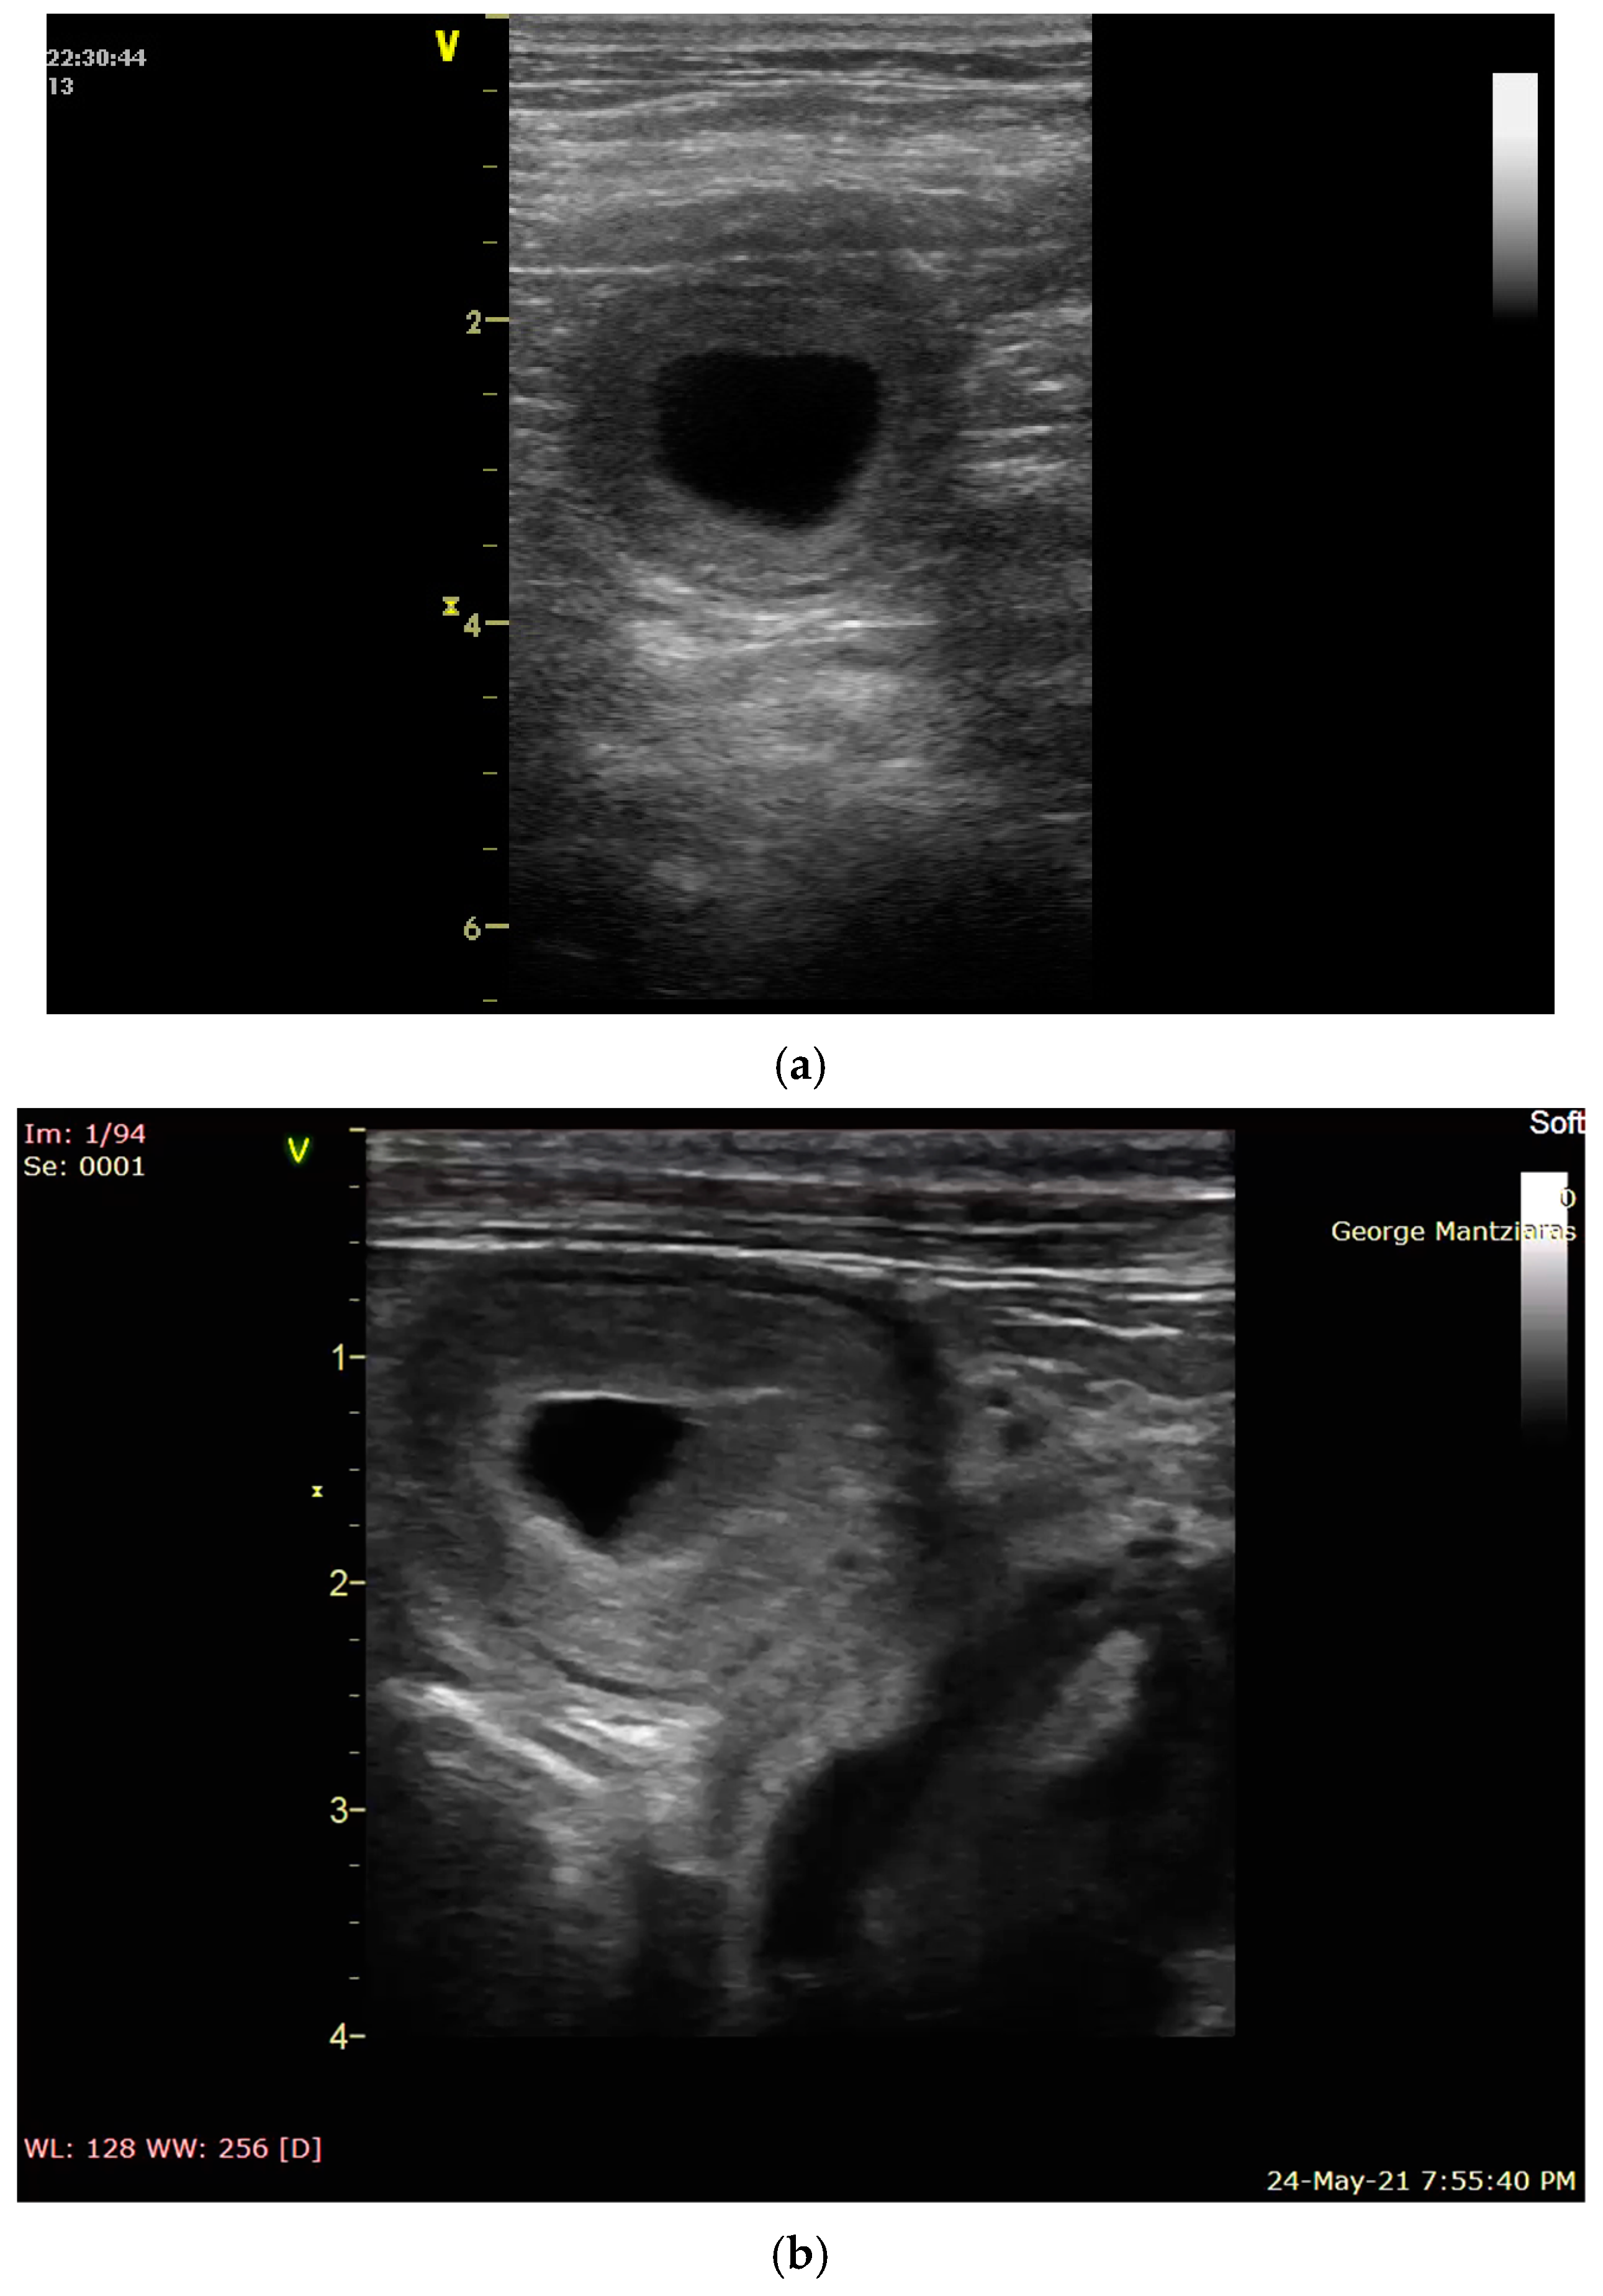

2.3. Uterine Pathology